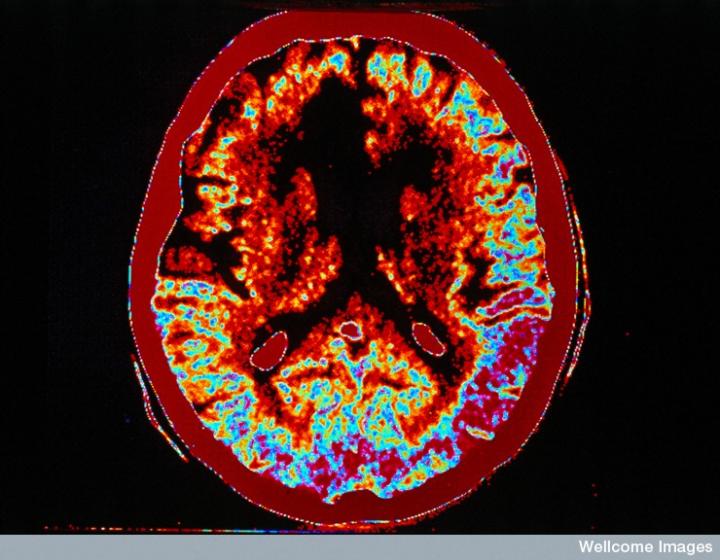

左側(cè)的血流圖比右側(cè)的X射線CT掃描顯示出更多的中風(fēng)損傷

慢性中風(fēng)患者的腦成像

CT掃描的主圖顯示左側(cè)有一些中風(fēng)損傷,由 Wellcome Images提供。Wellcome Photo Library提供的慢性中風(fēng)的附加圖像 ,Wellcome Images,QL 從胚胎干細(xì)胞培養(yǎng)的神經(jīng)元。Ying & A. Smith, Wellcome Images 和 Yirui Sun, Wellcome Images 移植的小鼠神經(jīng)干細(xì)胞。